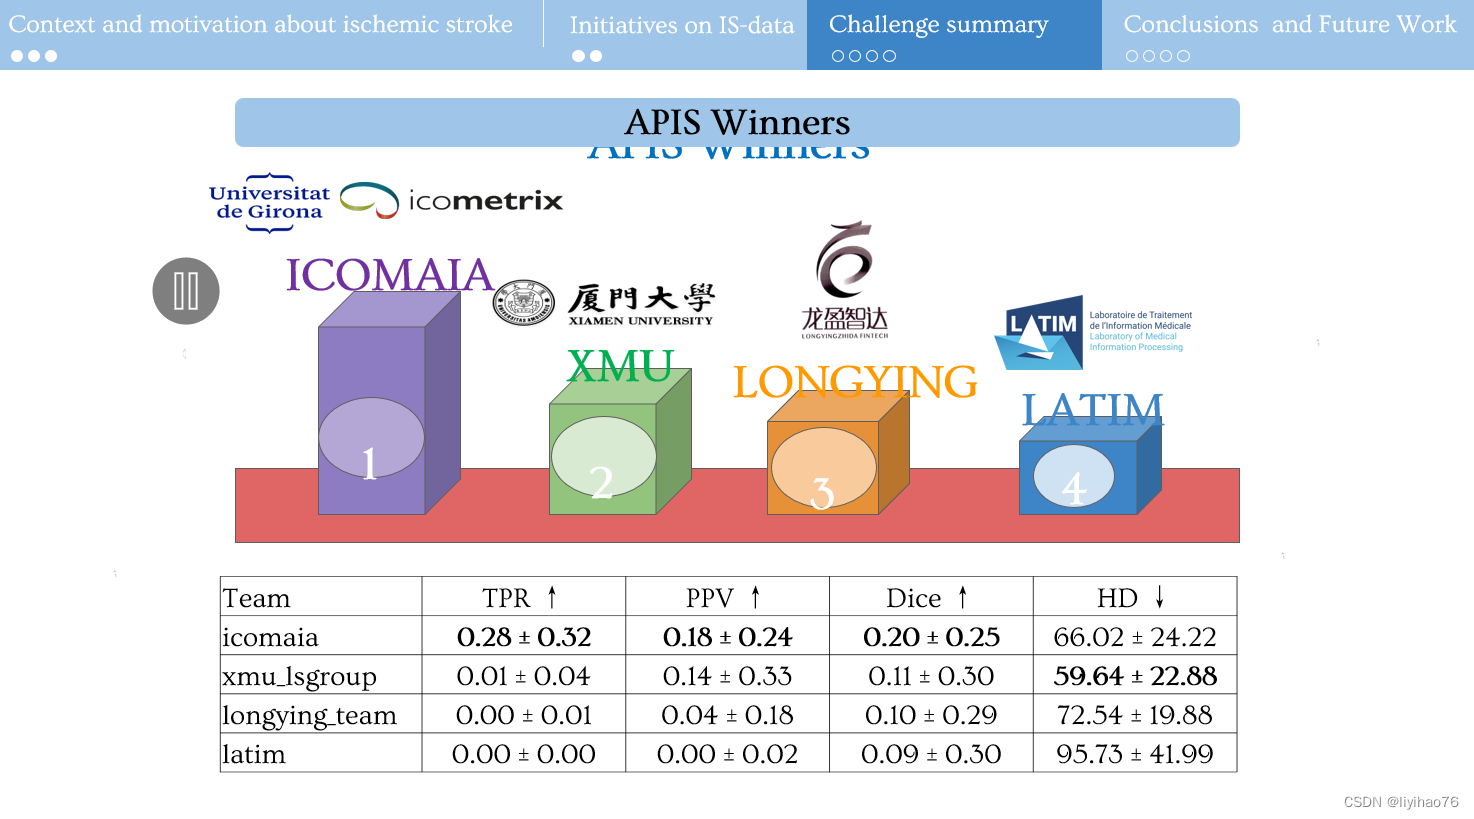

1.比赛任务及结果

5.比赛总结

- 由于病变的对比度差和低衰减,对缺血性中风 NCCT 序列的分割仍然具有挑战性。

- 目前在 ADC 序列上的工作可以以良好的性能分割病变,但在缺血病例的临床作用路径中是不可行的。

- 无论是模型、预处理还是其他方法都无法在 NCCT 序列上取得显着的结果。

- nnU-Net 在3D分割任务中依旧表现优异,数据预处理的不同可能会对分割表现有较大影响。